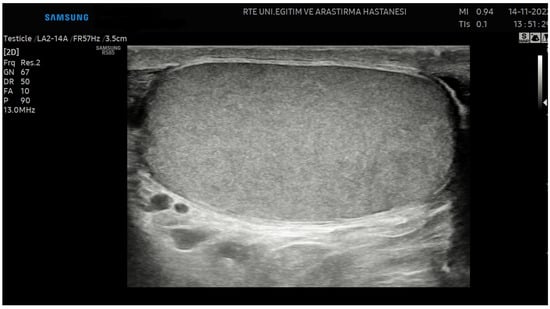

2.4. Testicular Ultrasonography

2.5. Image Preprocessing